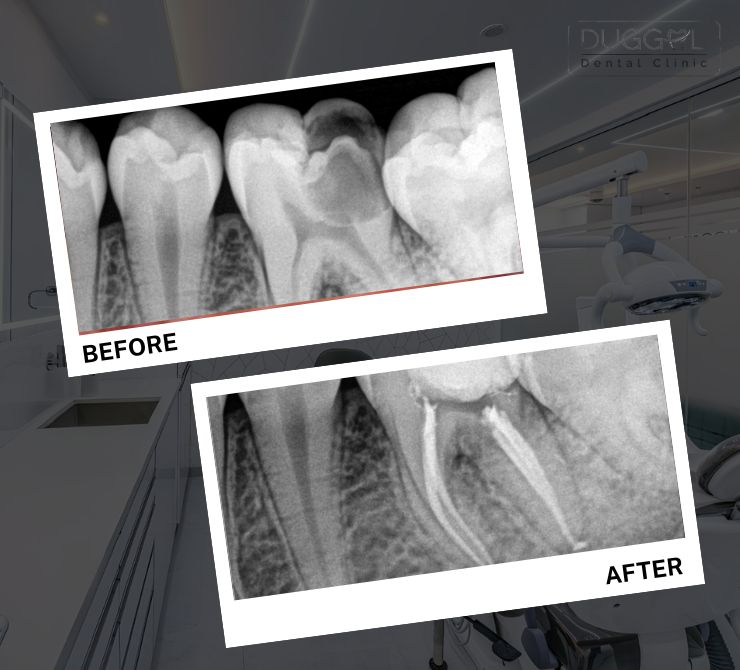

Root canal treatment is used to save your natural teeth from infection and tooth decay.

RCT’s are performed to relieve the pain of the tooth caused by inflammation or infection. And unlike old days, you can now experience painless root canal treatment in Pune Camp at Duggal dental clinic